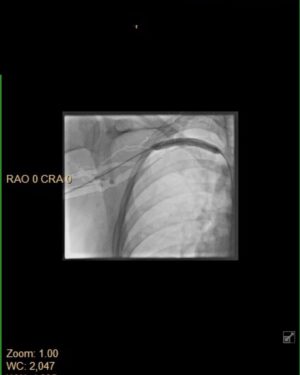

26.4K Likes – Justine Ezarik Instagram

Caption : OLD PHOTOS!! I am ok now!! Just my yearly reminder to you all that blood clots can be fatal! KNOW THE SIGNS, symptoms and if you’re possibly at risk. 3 years ago today there was a point that I wasn’t sure I’d make it but very grateful for the amazing care from doctors, support from friends and my sister who was there pretty much 24/7 with me! Thx @jennaezarik !! My diagnosis is thoracic outlet syndrome but there are many things that can lead to blood clots. Like prolonged immobility (long flights!), surgery, cancer, smoking, pregnancy, hormonal birth control, family history, obesity, age, genetic disorders and more. Signs and symptoms can vary depending on the location. Pain, swelling, redness, shortness of breath (if the clot travels to your lungs), headaches, weakness, numbness, difficulty speaking (it clot has traveled to your brain). Basically if you THINK something is wrong, don’t wait to seek help. I waited a few days after first noticing symptoms but brushed it off because I was “busy” 😳 I definitely won’t do that again! I have had to alter some activities I do to avoid possible repercussions but for the most part I am back and doing more than I ever have before! Took awhile to get back to this point but worth it 🙏🏻🩸Likes : 26432

26.4K Likes – Justine Ezarik Instagram

Caption : OLD PHOTOS!! I am ok now!! Just my yearly reminder to you all that blood clots can be fatal! KNOW THE SIGNS, symptoms and if you’re possibly at risk. 3 years ago today there was a point that I wasn’t sure I’d make it but very grateful for the amazing care from doctors, support from friends and my sister who was there pretty much 24/7 with me! Thx @jennaezarik !! My diagnosis is thoracic outlet syndrome but there are many things that can lead to blood clots. Like prolonged immobility (long flights!), surgery, cancer, smoking, pregnancy, hormonal birth control, family history, obesity, age, genetic disorders and more. Signs and symptoms can vary depending on the location. Pain, swelling, redness, shortness of breath (if the clot travels to your lungs), headaches, weakness, numbness, difficulty speaking (it clot has traveled to your brain). Basically if you THINK something is wrong, don’t wait to seek help. I waited a few days after first noticing symptoms but brushed it off because I was “busy” 😳 I definitely won’t do that again! I have had to alter some activities I do to avoid possible repercussions but for the most part I am back and doing more than I ever have before! Took awhile to get back to this point but worth it 🙏🏻🩸Likes : 26432

26.4K Likes – Justine Ezarik Instagram

Caption : OLD PHOTOS!! I am ok now!! Just my yearly reminder to you all that blood clots can be fatal! KNOW THE SIGNS, symptoms and if you’re possibly at risk. 3 years ago today there was a point that I wasn’t sure I’d make it but very grateful for the amazing care from doctors, support from friends and my sister who was there pretty much 24/7 with me! Thx @jennaezarik !! My diagnosis is thoracic outlet syndrome but there are many things that can lead to blood clots. Like prolonged immobility (long flights!), surgery, cancer, smoking, pregnancy, hormonal birth control, family history, obesity, age, genetic disorders and more. Signs and symptoms can vary depending on the location. Pain, swelling, redness, shortness of breath (if the clot travels to your lungs), headaches, weakness, numbness, difficulty speaking (it clot has traveled to your brain). Basically if you THINK something is wrong, don’t wait to seek help. I waited a few days after first noticing symptoms but brushed it off because I was “busy” 😳 I definitely won’t do that again! I have had to alter some activities I do to avoid possible repercussions but for the most part I am back and doing more than I ever have before! Took awhile to get back to this point but worth it 🙏🏻🩸Likes : 26432

26.4K Likes – Justine Ezarik Instagram

Caption : OLD PHOTOS!! I am ok now!! Just my yearly reminder to you all that blood clots can be fatal! KNOW THE SIGNS, symptoms and if you’re possibly at risk. 3 years ago today there was a point that I wasn’t sure I’d make it but very grateful for the amazing care from doctors, support from friends and my sister who was there pretty much 24/7 with me! Thx @jennaezarik !! My diagnosis is thoracic outlet syndrome but there are many things that can lead to blood clots. Like prolonged immobility (long flights!), surgery, cancer, smoking, pregnancy, hormonal birth control, family history, obesity, age, genetic disorders and more. Signs and symptoms can vary depending on the location. Pain, swelling, redness, shortness of breath (if the clot travels to your lungs), headaches, weakness, numbness, difficulty speaking (it clot has traveled to your brain). Basically if you THINK something is wrong, don’t wait to seek help. I waited a few days after first noticing symptoms but brushed it off because I was “busy” 😳 I definitely won’t do that again! I have had to alter some activities I do to avoid possible repercussions but for the most part I am back and doing more than I ever have before! Took awhile to get back to this point but worth it 🙏🏻🩸Likes : 26432

26.4K Likes – Justine Ezarik Instagram

Caption : OLD PHOTOS!! I am ok now!! Just my yearly reminder to you all that blood clots can be fatal! KNOW THE SIGNS, symptoms and if you’re possibly at risk. 3 years ago today there was a point that I wasn’t sure I’d make it but very grateful for the amazing care from doctors, support from friends and my sister who was there pretty much 24/7 with me! Thx @jennaezarik !! My diagnosis is thoracic outlet syndrome but there are many things that can lead to blood clots. Like prolonged immobility (long flights!), surgery, cancer, smoking, pregnancy, hormonal birth control, family history, obesity, age, genetic disorders and more. Signs and symptoms can vary depending on the location. Pain, swelling, redness, shortness of breath (if the clot travels to your lungs), headaches, weakness, numbness, difficulty speaking (it clot has traveled to your brain). Basically if you THINK something is wrong, don’t wait to seek help. I waited a few days after first noticing symptoms but brushed it off because I was “busy” 😳 I definitely won’t do that again! I have had to alter some activities I do to avoid possible repercussions but for the most part I am back and doing more than I ever have before! Took awhile to get back to this point but worth it 🙏🏻🩸Likes : 26432

26.4K Likes – Justine Ezarik Instagram

Caption : OLD PHOTOS!! I am ok now!! Just my yearly reminder to you all that blood clots can be fatal! KNOW THE SIGNS, symptoms and if you’re possibly at risk. 3 years ago today there was a point that I wasn’t sure I’d make it but very grateful for the amazing care from doctors, support from friends and my sister who was there pretty much 24/7 with me! Thx @jennaezarik !! My diagnosis is thoracic outlet syndrome but there are many things that can lead to blood clots. Like prolonged immobility (long flights!), surgery, cancer, smoking, pregnancy, hormonal birth control, family history, obesity, age, genetic disorders and more. Signs and symptoms can vary depending on the location. Pain, swelling, redness, shortness of breath (if the clot travels to your lungs), headaches, weakness, numbness, difficulty speaking (it clot has traveled to your brain). Basically if you THINK something is wrong, don’t wait to seek help. I waited a few days after first noticing symptoms but brushed it off because I was “busy” 😳 I definitely won’t do that again! I have had to alter some activities I do to avoid possible repercussions but for the most part I am back and doing more than I ever have before! Took awhile to get back to this point but worth it 🙏🏻🩸Likes : 26432

26.4K Likes – Justine Ezarik Instagram

Caption : OLD PHOTOS!! I am ok now!! Just my yearly reminder to you all that blood clots can be fatal! KNOW THE SIGNS, symptoms and if you’re possibly at risk. 3 years ago today there was a point that I wasn’t sure I’d make it but very grateful for the amazing care from doctors, support from friends and my sister who was there pretty much 24/7 with me! Thx @jennaezarik !! My diagnosis is thoracic outlet syndrome but there are many things that can lead to blood clots. Like prolonged immobility (long flights!), surgery, cancer, smoking, pregnancy, hormonal birth control, family history, obesity, age, genetic disorders and more. Signs and symptoms can vary depending on the location. Pain, swelling, redness, shortness of breath (if the clot travels to your lungs), headaches, weakness, numbness, difficulty speaking (it clot has traveled to your brain). Basically if you THINK something is wrong, don’t wait to seek help. I waited a few days after first noticing symptoms but brushed it off because I was “busy” 😳 I definitely won’t do that again! I have had to alter some activities I do to avoid possible repercussions but for the most part I am back and doing more than I ever have before! Took awhile to get back to this point but worth it 🙏🏻🩸Likes : 26432

26.4K Likes – Justine Ezarik Instagram

Caption : OLD PHOTOS!! I am ok now!! Just my yearly reminder to you all that blood clots can be fatal! KNOW THE SIGNS, symptoms and if you’re possibly at risk. 3 years ago today there was a point that I wasn’t sure I’d make it but very grateful for the amazing care from doctors, support from friends and my sister who was there pretty much 24/7 with me! Thx @jennaezarik !! My diagnosis is thoracic outlet syndrome but there are many things that can lead to blood clots. Like prolonged immobility (long flights!), surgery, cancer, smoking, pregnancy, hormonal birth control, family history, obesity, age, genetic disorders and more. Signs and symptoms can vary depending on the location. Pain, swelling, redness, shortness of breath (if the clot travels to your lungs), headaches, weakness, numbness, difficulty speaking (it clot has traveled to your brain). Basically if you THINK something is wrong, don’t wait to seek help. I waited a few days after first noticing symptoms but brushed it off because I was “busy” 😳 I definitely won’t do that again! I have had to alter some activities I do to avoid possible repercussions but for the most part I am back and doing more than I ever have before! Took awhile to get back to this point but worth it 🙏🏻🩸Likes : 26432